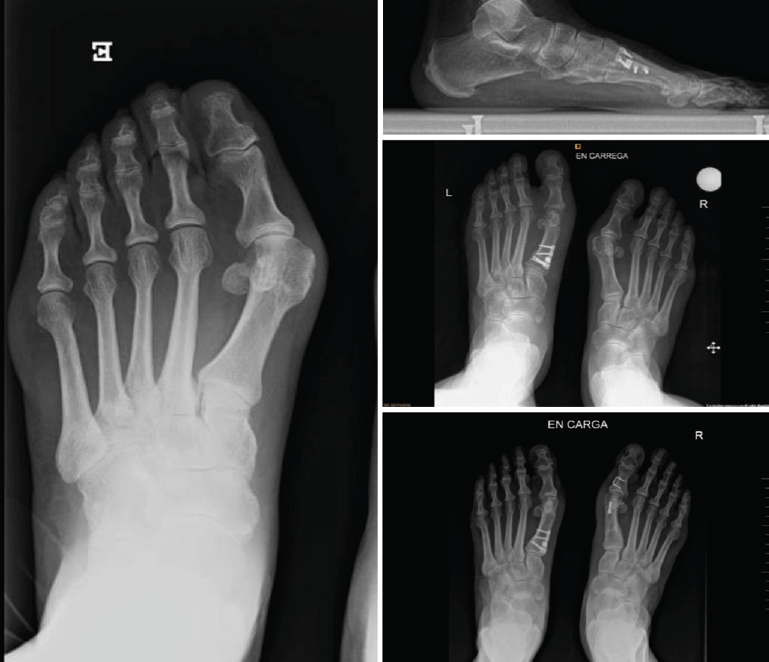

Figura 4. Caso clínico de osteotomía de apertura medial (radiología preoperatoria y control a los 6 años y 8 meses).

En las Figuras 4 y 5 se muestra un ejemplo intervenido de osteotomía de apertura y cierre.

Se han realizado 22 osteotomías proximales (15 de apertura y 7 de cierre). La puntuación de la AOFAS preoperatoria de estos pacientes era de 54, aumentando a 92 en el control realizado en el momento de la revisión (6 años y 8 meses de media); esto supone un incremento del 70%. Radiográficamente, el ángulo intermetatarsiano prequirúrgico medio era de 19° y el posquirúrgico medio era de 11,7°; por tanto, una corrección media de 7,3°. Además, ha existido un alargamiento del metatarsiano de 3 mm en las osteotomías de apertura y una disminución de 6 mm en las osteotomías de cierre (Tabla 2).